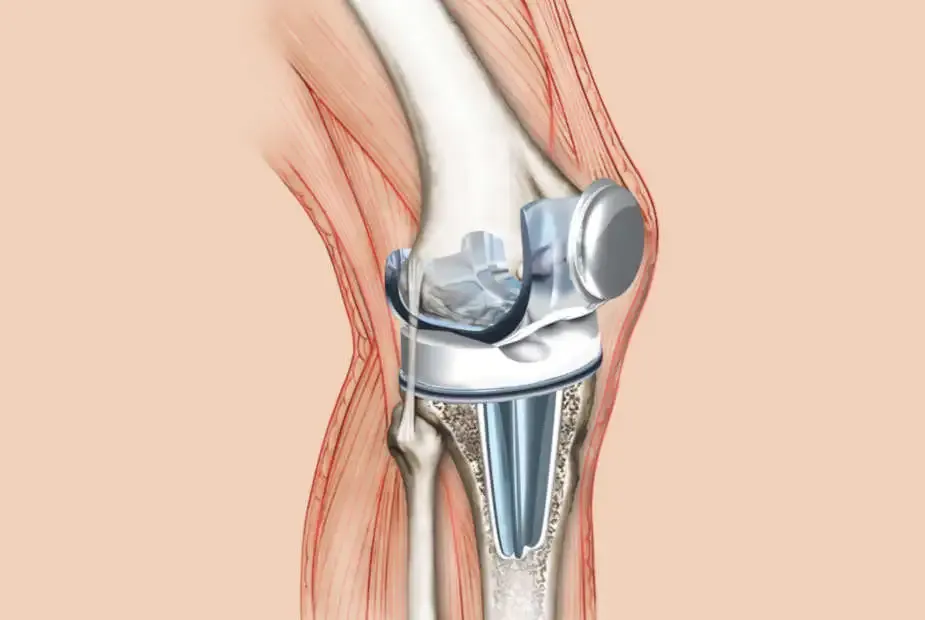

Ból po endoprotezie kolana jest częścią naturalnego procesu zdrowienia, który każdy pacjent musi przejść. Zrozumienie różnych faz bólu może pomóc w lepszym przygotowaniu się do rekonstrukcji i rehabilitacji. Ważne jest, aby wiedzieć, jak długo trwa ból po endoprotezie kolana, ponieważ to pozwala pacjentom na realistyczne oczekiwania dotyczące powrotu do pełnej sprawności.

Bezpośrednio po operacji pacjenci doświadczają silnego bólu, który jest często największym wyzwaniem w okresie rekonwalescencji. Ból ten może być tak intensywny, że pacjenci potrzebują regularnego stosowania leków przeciwbólowych i chłodnych okładów, aby go złagodzić. Rekomendacje dotyczące leczenia bólu w tym okresie są kluczowe dla komfortu pacjenta i jego zdolności do rozpoczęcia rehabilitacji.

W pierwszych dniach po operacji pacjenci powinni być świadomi, że ból jest naturalny i towarzyszy procesowi gojenia. Stosowanie leków zgodnie z zaleceniami lekarza oraz wykonywanie ćwiczeń oddechowych może pomóc w złagodzeniu objawów. Warto również dbać o wizyty kontrolne, aby lekarz mógł monitorować stan zdrowia pacjenta.